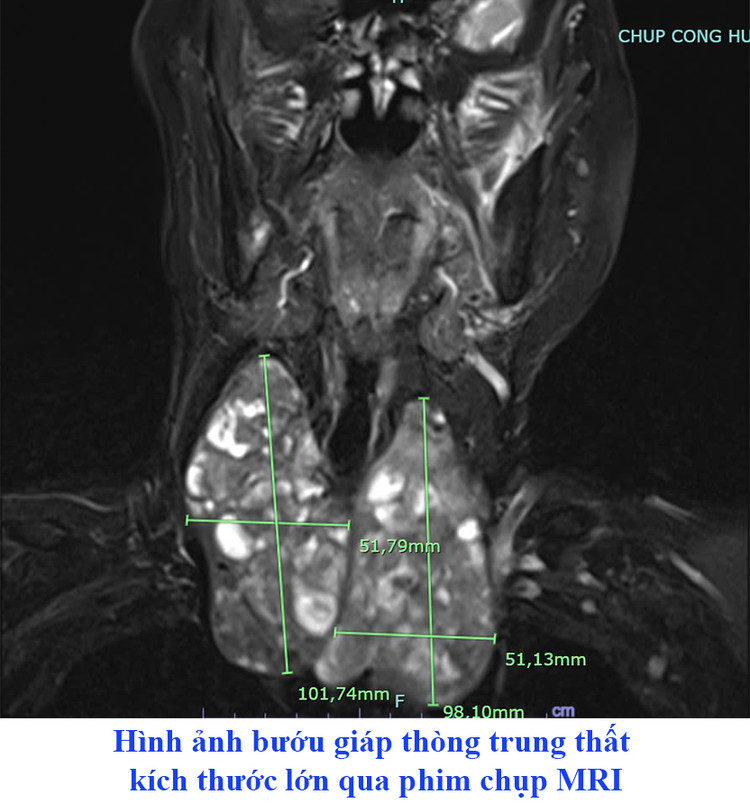

Khoa Phẫu thuật tim mạch – Lồng ngực – Bệnh viện đa khoa tỉnh Phú Thọ vừa thực hiện phẫu thuật cắt bướu tuyến giáp khổng lồ thòng trung thất với kích thước 2 thùy lần lượt là 102 x 52mm (phải) và 98x51mm cho người bệnh nữ 72 tuổi.

Tại đây, hình ảnh chụp cộng hưởng từ lồng ngực cho thấy cả hai thuỳ tuyến giáp rất to, thòng xuống trung thất. Kết quả siêu âm tuyến giáp và chọc hút kim nhỏ trước mổ cho kết quả bướu giáp keo.

Người bệnh được chẩn đoán: Bướu giáp thòng trung thất và được bác sĩ chỉ định phẫu thuật cắt toàn bộ bướu giáp thòng trung thất.